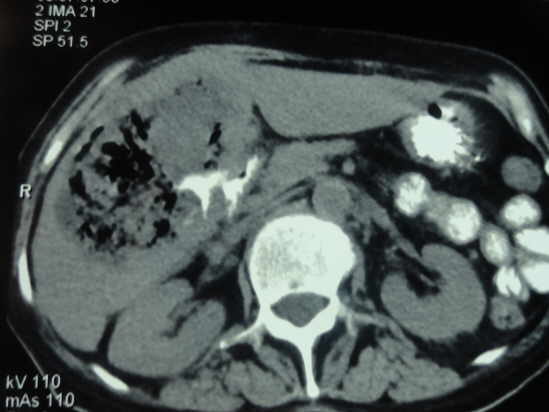

Tomografía Axial Computarizada de Absceso Hepático Amebiano

La sintomatología del absceso hepático amibiano se ha englobado en lo que se denomina la “triada clásica”: hepatomegalia, dolor en hipocondrio derecho y fiebre, asociados a leucocitosis en presencia de neutrofilia y pruebas serológicas para E. histolytica positivas.